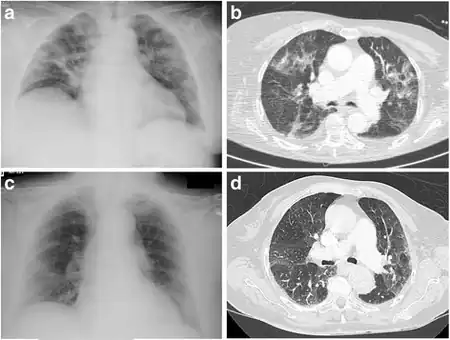

Eosinophilic pneumonia is diagnosed in one of three circumstances: when a complete blood count reveals increased eosinophils and a chest X-ray or computed tomography identifies abnormalities in the lungs, when a biopsy identifies increased eosinophils in lung tissue, or when increased eosinophils are found in fluid obtained by a bronchoscopy (bronchoalveolar lavage fluid). Association with medication or cancer is usually apparent after review of a person's medical history. Specific parasitic infections are diagnosed after examining a person's exposure to common parasites and performing laboratory tests to look for likely causes. If no underlying cause is found, a diagnosis of acute or chronic eosinophilic pneumonia is made based upon the following criteria. Acute eosinophilic pneumonia is most likely with respiratory failure after an acute febrile illness of usually less than one week, changes in multiple areas and fluid in the area surrounding the lungs on a chest X-ray, and eosinophils comprising more than 25% of white blood cells in fluid obtained by bronchoalveolar lavage. Other typical laboratory abnormalities include an elevated white blood cell count, erythrocyte sedimentation rate, and immunoglobulin G level. Pulmonary function testing usually reveals a restrictive process with reduced diffusion capacity for carbon monoxide. Chronic eosinophilic pneumonia is most likely when the symptoms have been present for more than a month. Laboratory tests typical of chronic eosinophilic pneumonia include increased levels of eosinophils in the blood, a high erythrocyte sedimentation rate, iron deficiency anemia, and increased platelets. A chest X-ray can show abnormalities anywhere, but the most specific finding is increased shadow in the periphery of the lungs, away from the heart.